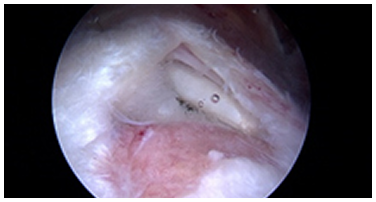

관절내시경

관절내시경은 무릎과 어깨뿐만 아니라 최근에는 팔꿈치, 손목, 발목 등 작은 관절에서도 관절 질환을 진단하고 치료하는 데 매우 유용한 방법입니다.

약 5mm 정도의 작은 피부 절개를 통해 초소형 카메라와 수술 도구가 장착된 내시경을 관절 내부로 삽입하여 병변을 직접 확인한 후, 치료 방법을 결정하여 병변을 제거하거나 복원하는 치료를 시행합니다. 절개가 거의 없어 제한된 부위 내에서 수술이 이루어지므로, 난이도가 높은 경우가 많아 반드시 숙련된 내시경 전문의에게 수술을 받아야 만족스러운 결과를 기대할 수 있습니다.

장점

1. 추가적인 마취나 복잡한 준비 없이 시술 가능

2. 피부 절개가 거의 없어 입원 기간이 짧고 회복 속도가 빠름

3. 부작용 위험이 낮고, 재발 가능성이 적음

4. 자기 관절을 최대한 보존할 수 있어 통증이 적음

5. 절개 부위가 작아 고령 환자도 부담 없이 수술 가능

관절내시경이미지

관절 내시경은 무릎과 어깨뿐만 아니라 팔꿈치, 손목, 발목 등 작은 관절의 질환까지 진단과 치료를 동시에 할 수 있는 매우 유용한 방법입니다.

약 5mm 정도의 피부 절개를 통해 초소형 카메라와 수술 도구가 부착된 내시경을 삽입하여, 관절 내부의 병변을 확인한 후 이를 제거하거나 봉합하는 치료를 진행합니다. 절개가 거의 없어 제한된 부위 내에서 수술을 시행하기 때문에 수술의 난이도가 높은 경우가 많이 있어 반드시 숙련된 내시경 전문의에게 수술을 받아야 만족할 만한 결과를 보장할 수 있습니다.